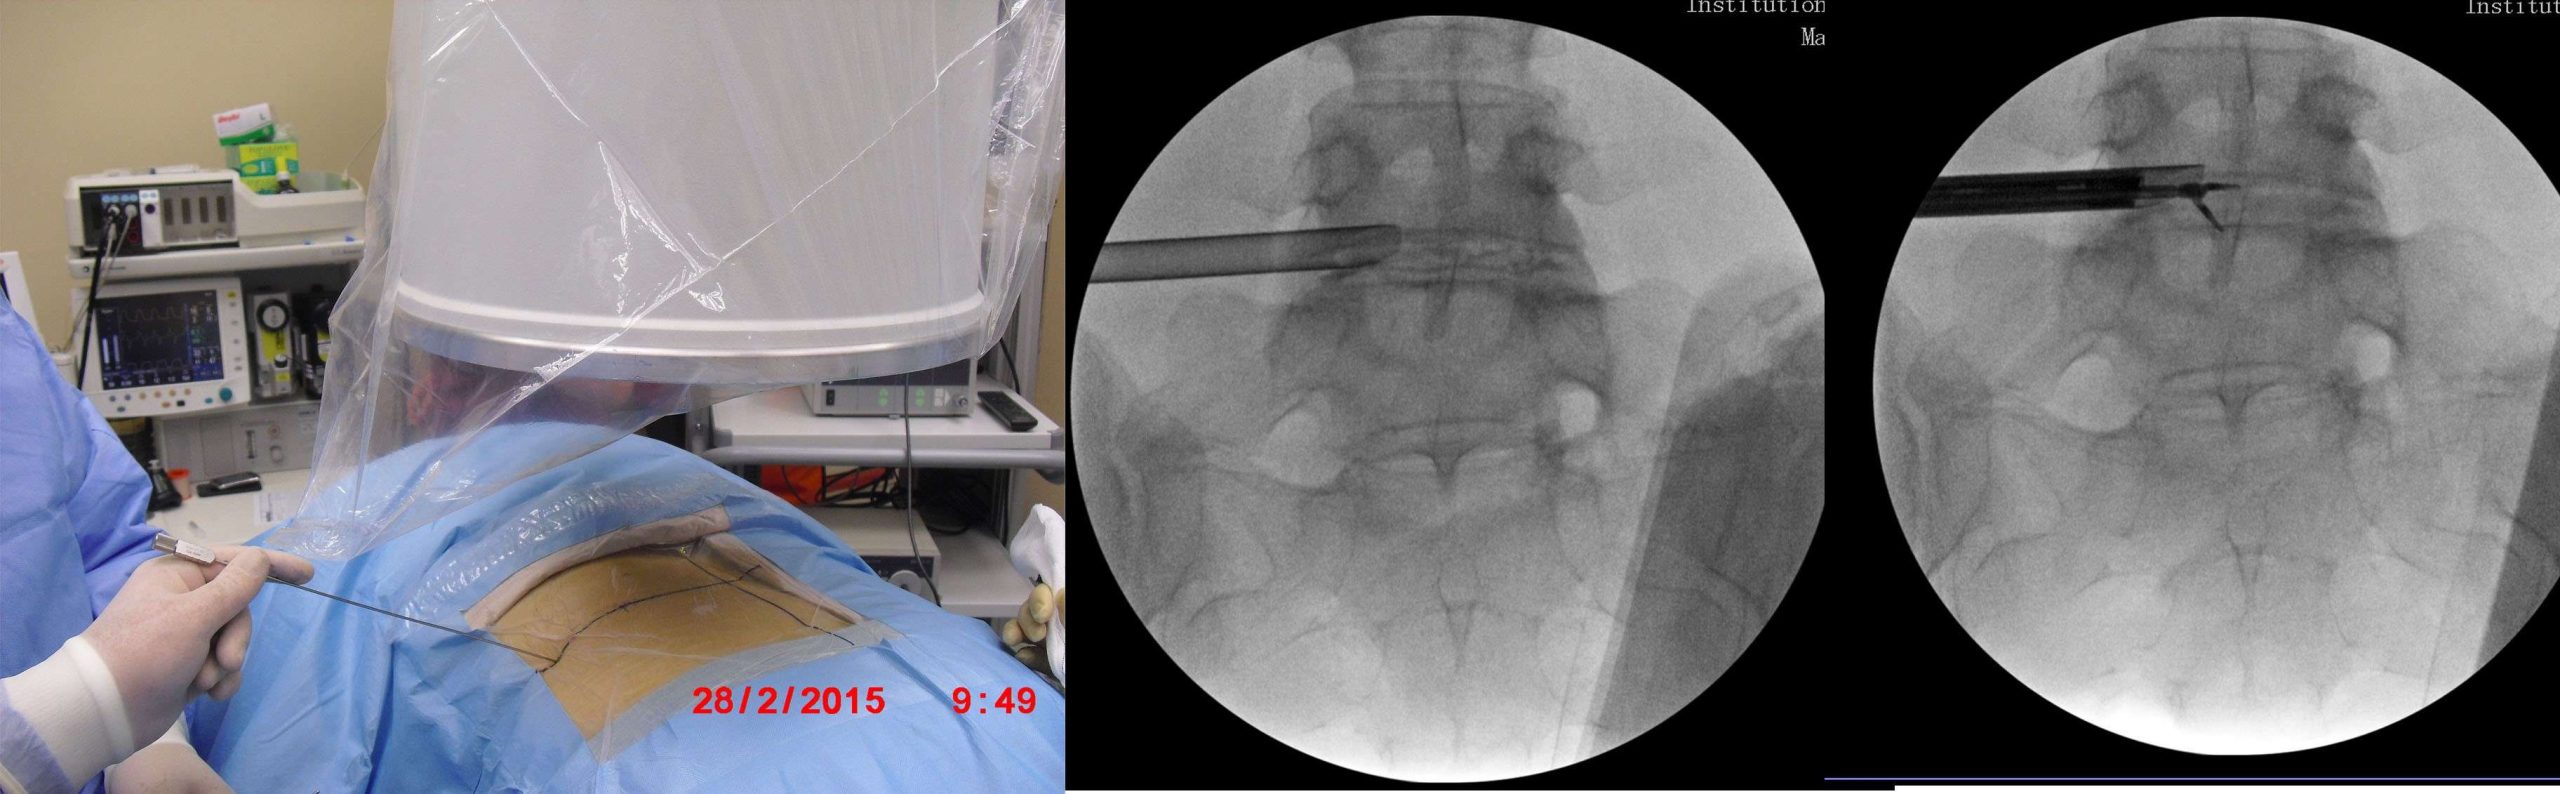

Tam kapalı bel fıtığı ameliyatı (KEBFA) ameliyathanede, radyolojik ve endoskopik görünteleme cihazları kullanılarak uygulanır.

Hasta yüzüstü pozisyonda özel bir masada ameliyat edilir. Önce radyolojik görüntüleme altında yandan bir iğne ile diske girilir. Indigo Carmin denilen bir boya ile disk boyanır ve sırasıyla obturator ve çalışma kanülü diske yerleştirilir.

Çalışma kanulünden kamera (Endoskop) ilerletilerek kamerada bulunan kanal içinden özel aletlerle ameliyat tamamlanır. Ameliyat süresi tipik bir vakada 45 dakikadır.